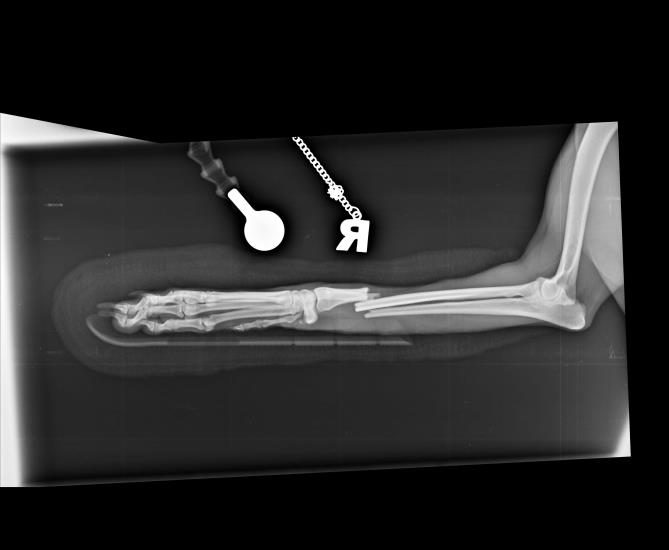

Dog leg fracture xray. Canine radius and ulna limb fracture radiograph

X ray. Radius and Ulna fracture in a Dog. Dog Leg Fracture. Radiography Radius Ulna Fracture Dog Splint this video show how to apply a splint that will be functional and comfortable (therefore well tolerated by the dog and the owner!). as mentioned earlier, distal radius/ulna fractures, especially those in small and toy breed dogs, addressed with external coaptation alone commonly result in malalignment or nonunion. — 1) any toy breed dog with a radius. Radius Ulna Fracture Dog Splint.